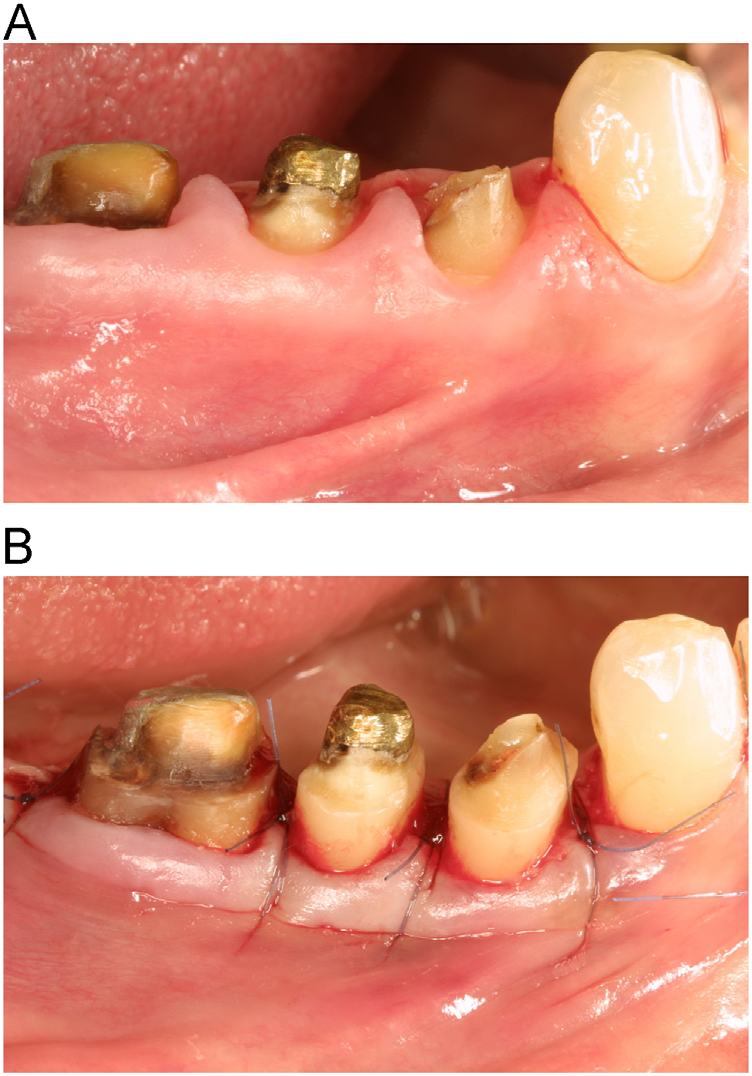

Surgical Crown Lengthening by Dr. Cirimpei Vasile Dentaltown Dental Code For Crown Lengthening This paper presents a minimally invasive technique for crown lengthening for short clinical crowns concurrent with excessive maxillary gingival display,. Ensures proper fit of dental restorations — by exposing more tooth structure, crown lengthening ensures that dental crowns and bridges can be properly fitted, promoting longevity and functionality. The procedure involves a tissue flap, which removes bone and soft tissue. Dental Code For Crown Lengthening.